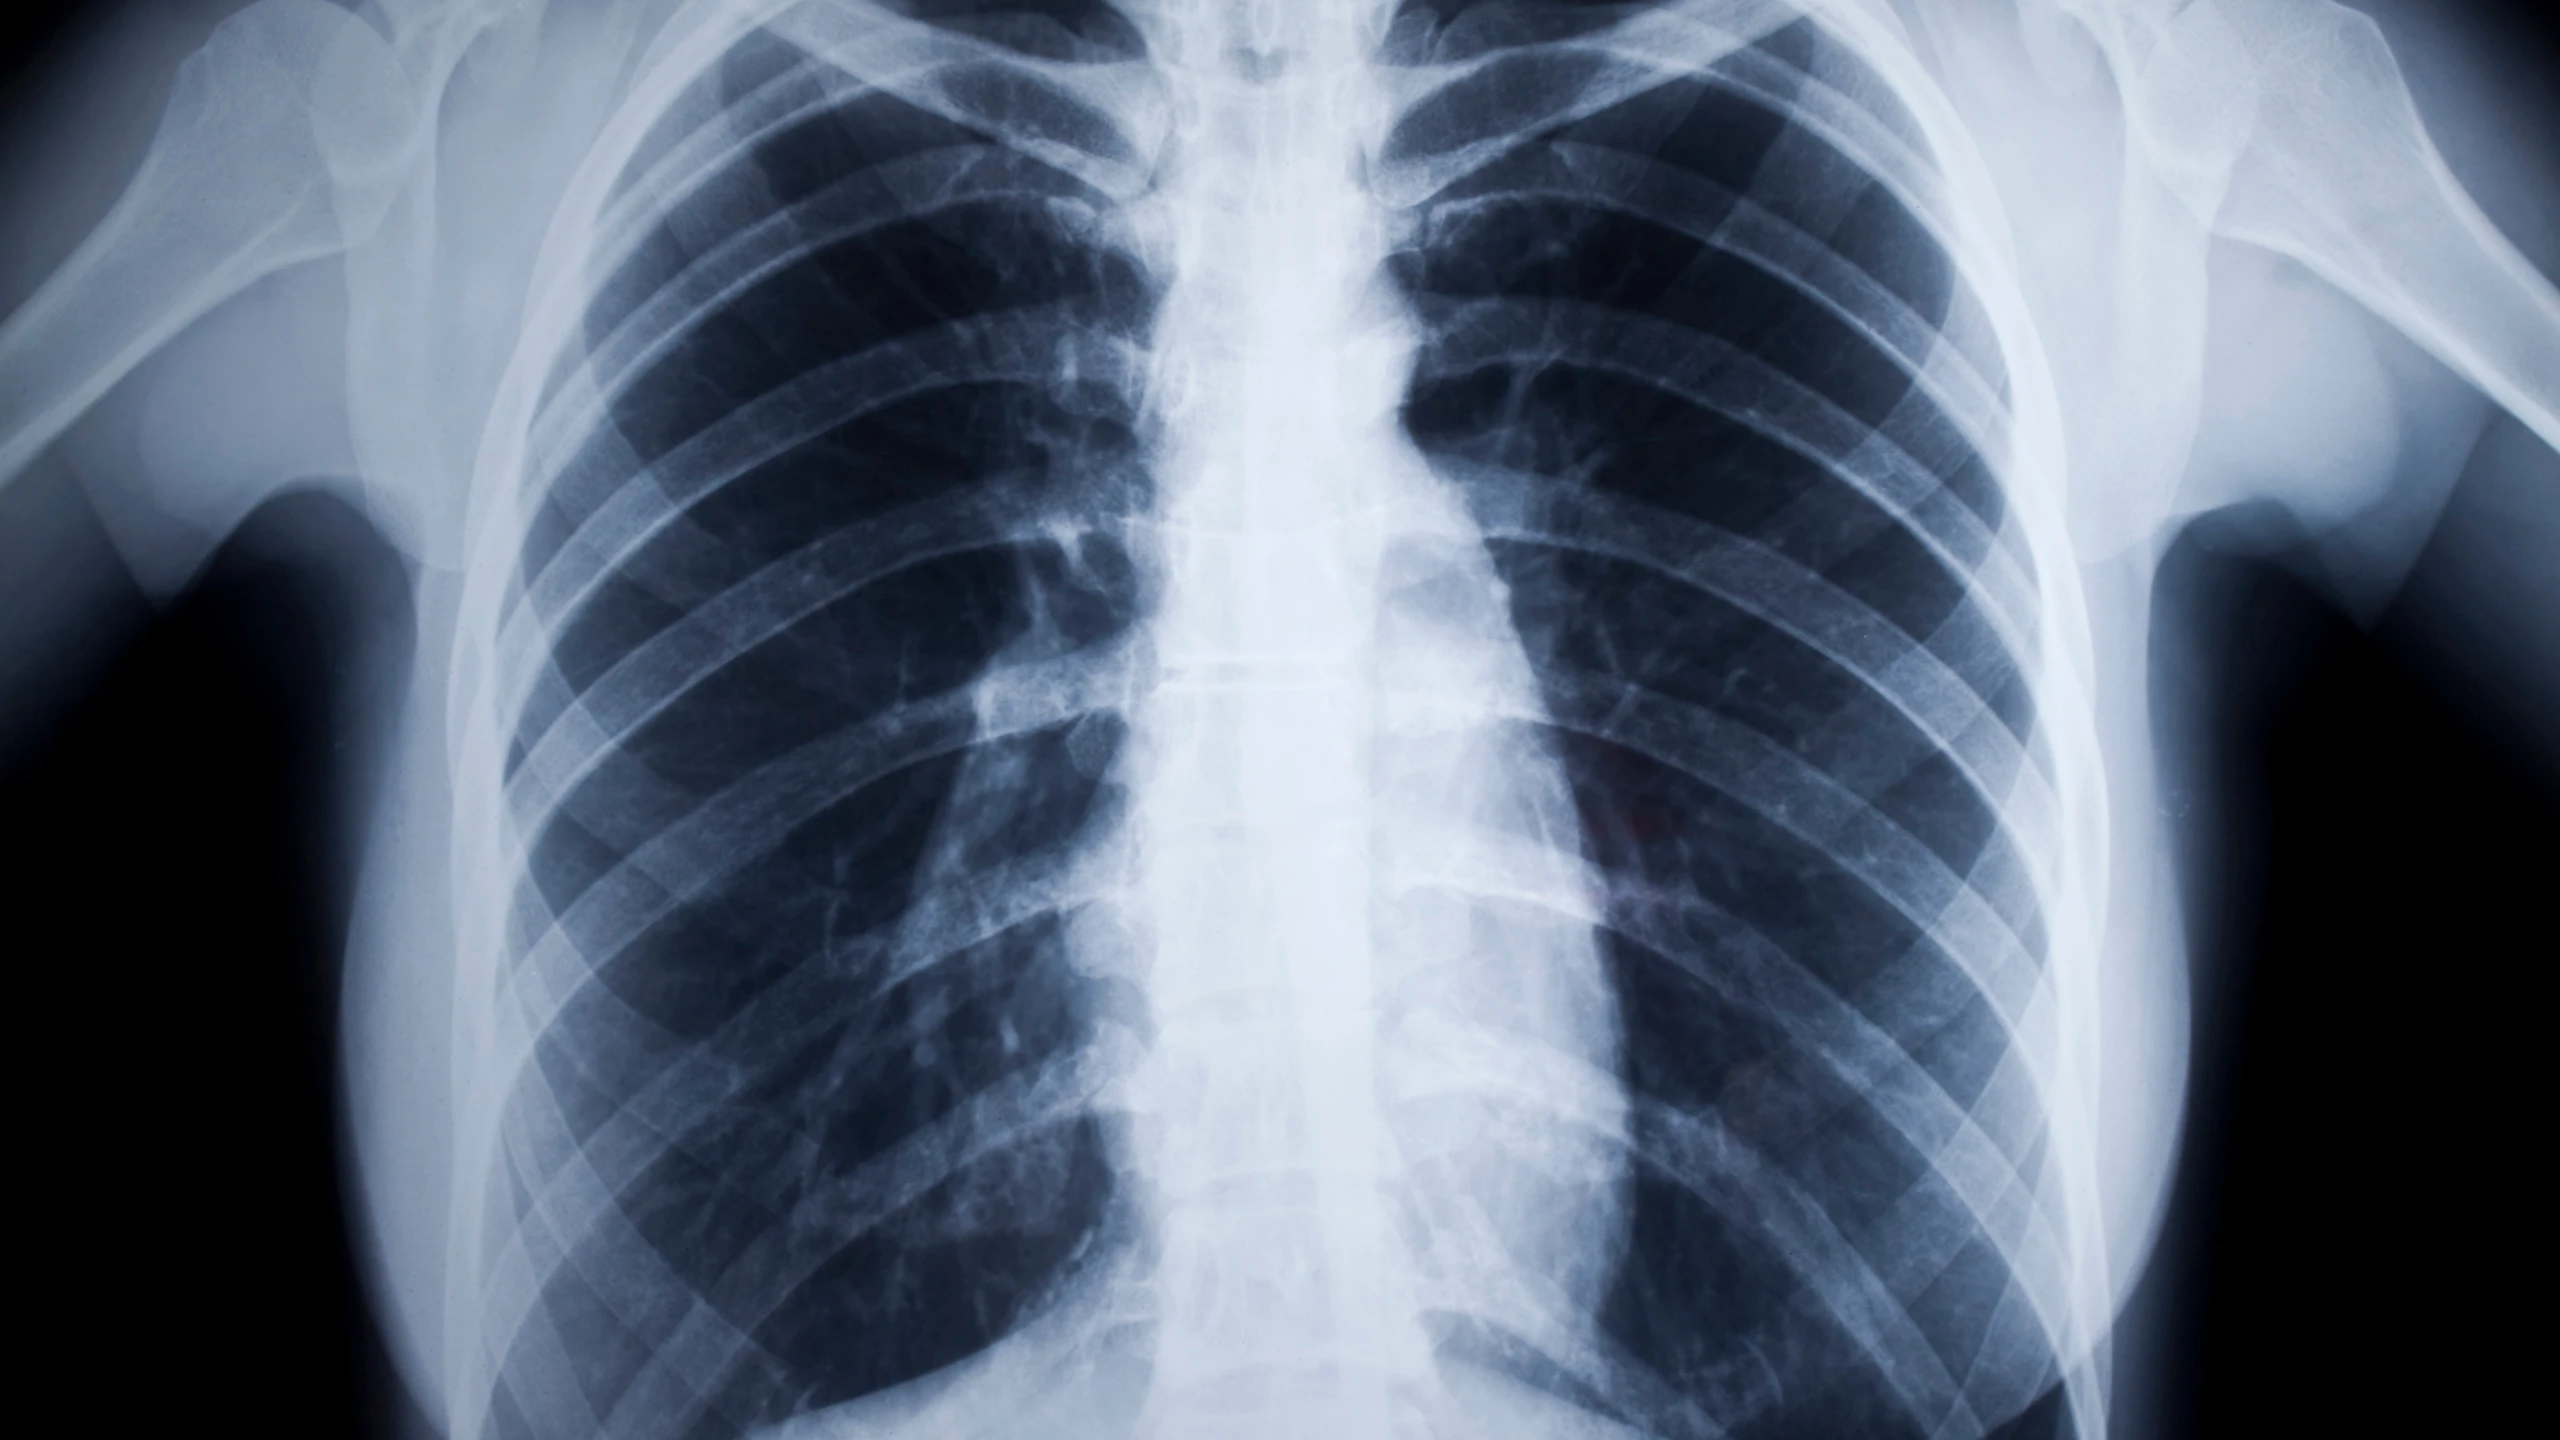

Giãn phế quản là một bệnh lý về phổi thường gặp, thông thường bệnh tiến triển mạn tính với những đợt cấp (ho, khó thở, khạc đờm) xen kẽ. Giãn phế quản nếu không được chẩn đoán và điều trị kịp thời có thể gây ra những biến chứng nguy hiểm. Vậy làm thế nào để nhận biết được bệnh giãn phế quản và điều trị như thế nào? Bạn có thể tham khảo bài viết dưới đây.

Giãn phế quản là một bệnh lý về phổi gây ho có đờm. Đây là tình trạng những ống phế quản của phổi bị tổn thương, dày lên và giãn rộng ra, tạo điều kiện thuận lợi cho vi khuẩn và chất nhầy tích tụ lại trong phổi của người bệnh. Điều này dẫn tới thường xuyên bị nhiễm trùng và tắc nghẽn đường thở.

Giãn phế quản là một tình trạng không hồi phục, nhưng vẫn có thể kiểm soát được. Tuy nhiên, khi giãn phế quản bùng phát, người bệnh cần được điều trị nhanh chóng để có thể duy trì được lưu lượng oxy tới cơ thể và ngăn ngừa được những tổn thương của phổi.